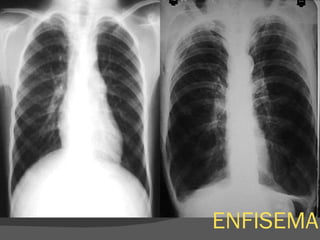

ENFISEMA